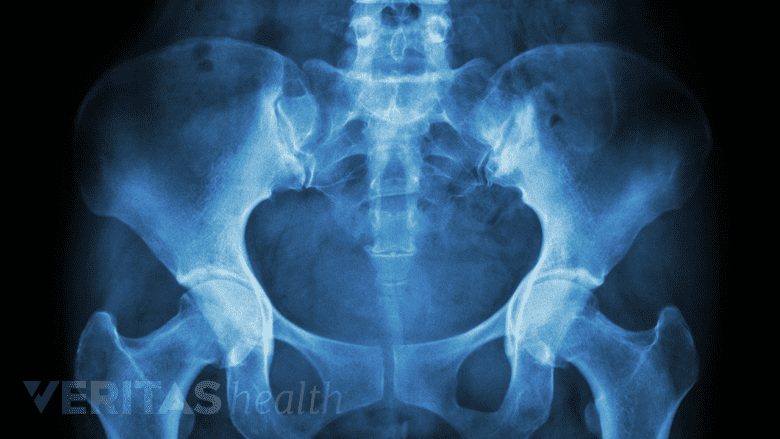

X-rays assist in diagnosing pain by detecting degenerative changes, and fractures.

- X-ray, which shows details of the bony structures in the spine. An x-ray particularly useful in identifying degenerative changes or fractures and can help identify certain types of rheumatological causes of pain (such as osteoarthritis). Flexion and extension X-rays may also be ordered if spinal instability is suspected.